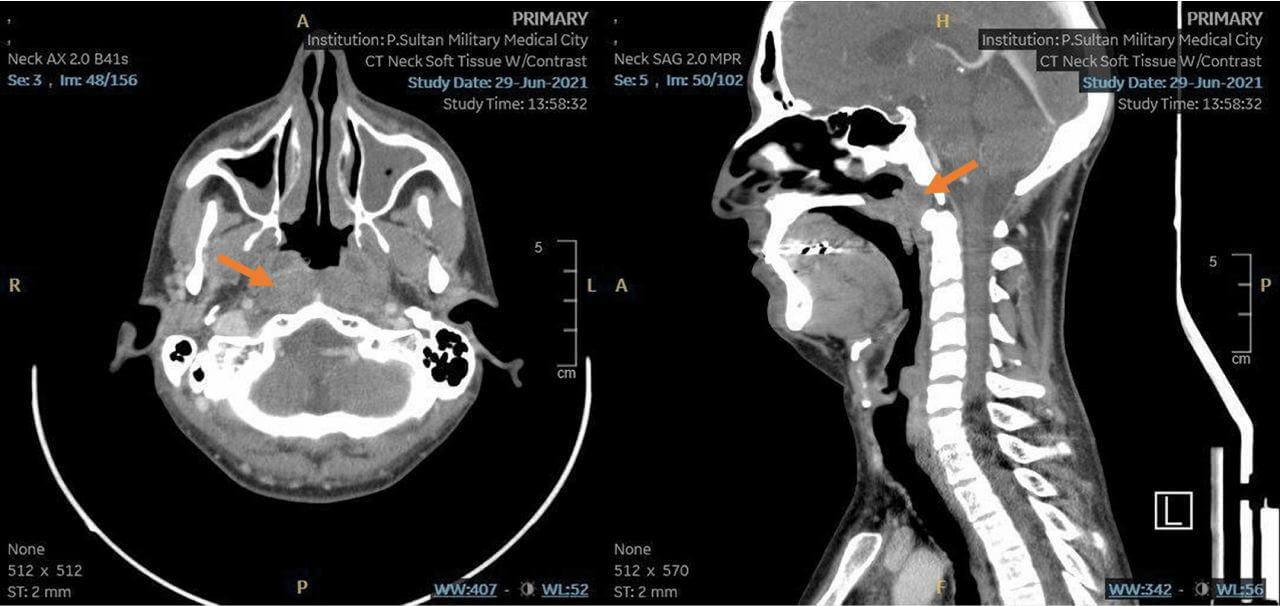

Careful collection of anamnesis and physical examination of the head and neck are fundamentally important and determine the further scope of diagnostic measures. If a suspicious mass is found in the mouth, oropharynx, thyroid gland, or hypopharynx, a computed tomography (CT) scan of the neck with intravenous contrast should be performed. CT well identifies bone invasion and allows assessment of appropriate regional lymphatic basins, and is often necessary for radiotherapy planning [4]. At the same time, CT is less accurate in assessing the prevalence of soft tissue injury and its resolution may not be sufficient to detect extremely small tumors, whereby magnetic resonance imaging (MRI) or positron emission tomography combined with CT (PET-CT) may be more informative [5].

MRI of the face and neck is the best method to estimate primary tumor prevalence (T-stage) as accurately as possible. Histological verification is mandatory for accurate staging and treatment planning. It is usually performed by endoscopic biopsy of nasopharynx formation under local or general anesthesia.